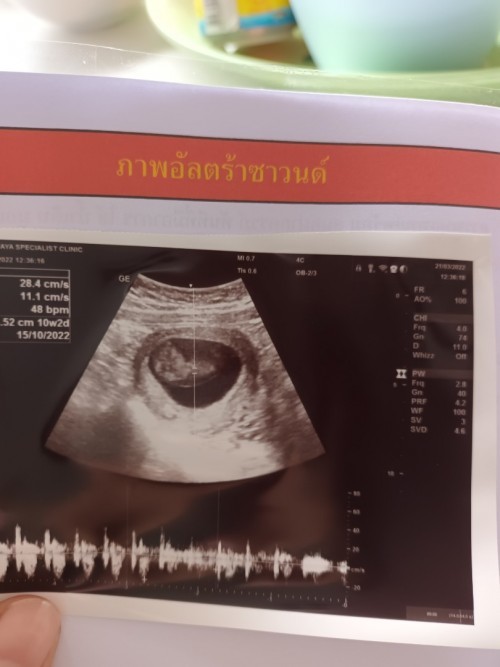

ตอนนี้ 10+1 แล้วจ้า

10w ค่ะ น้องยาว 3 ซม.

10week4dayค่ะ ขนาด3.1เซน